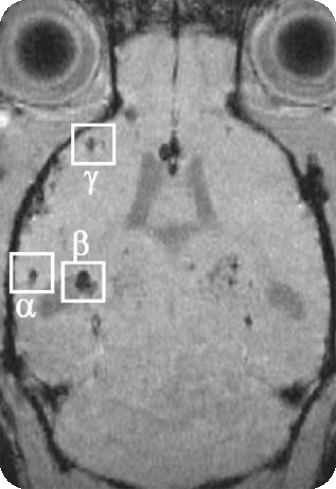

4、SWI磁敏感成像

磁敏感成像可大大提高磁敏感性,可用于检测老年痴呆小鼠模型粥状淀粉沉积斑块,评价药物作用疗效。

老年痴呆小鼠脑部的磁敏感成像: